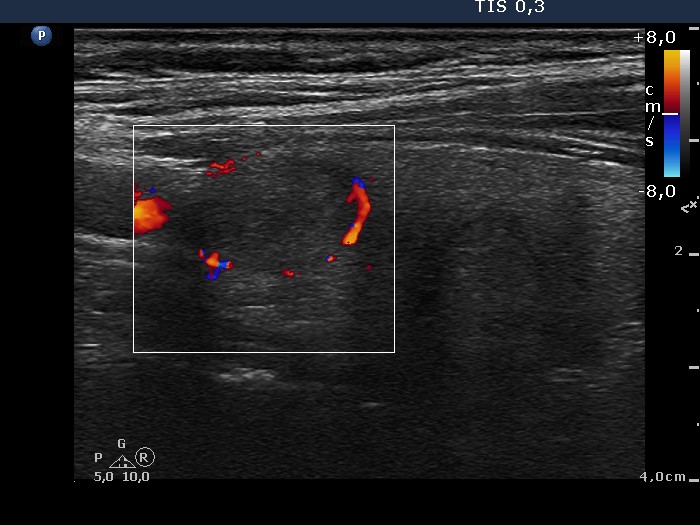

Benign nodular hyperplasia - Case 59. (ultrasonographic picture 5)

Upper part of the right lobe, longitudinal scan, color Doppler mode. The nodule in the upper part presents perinodular blood flow.